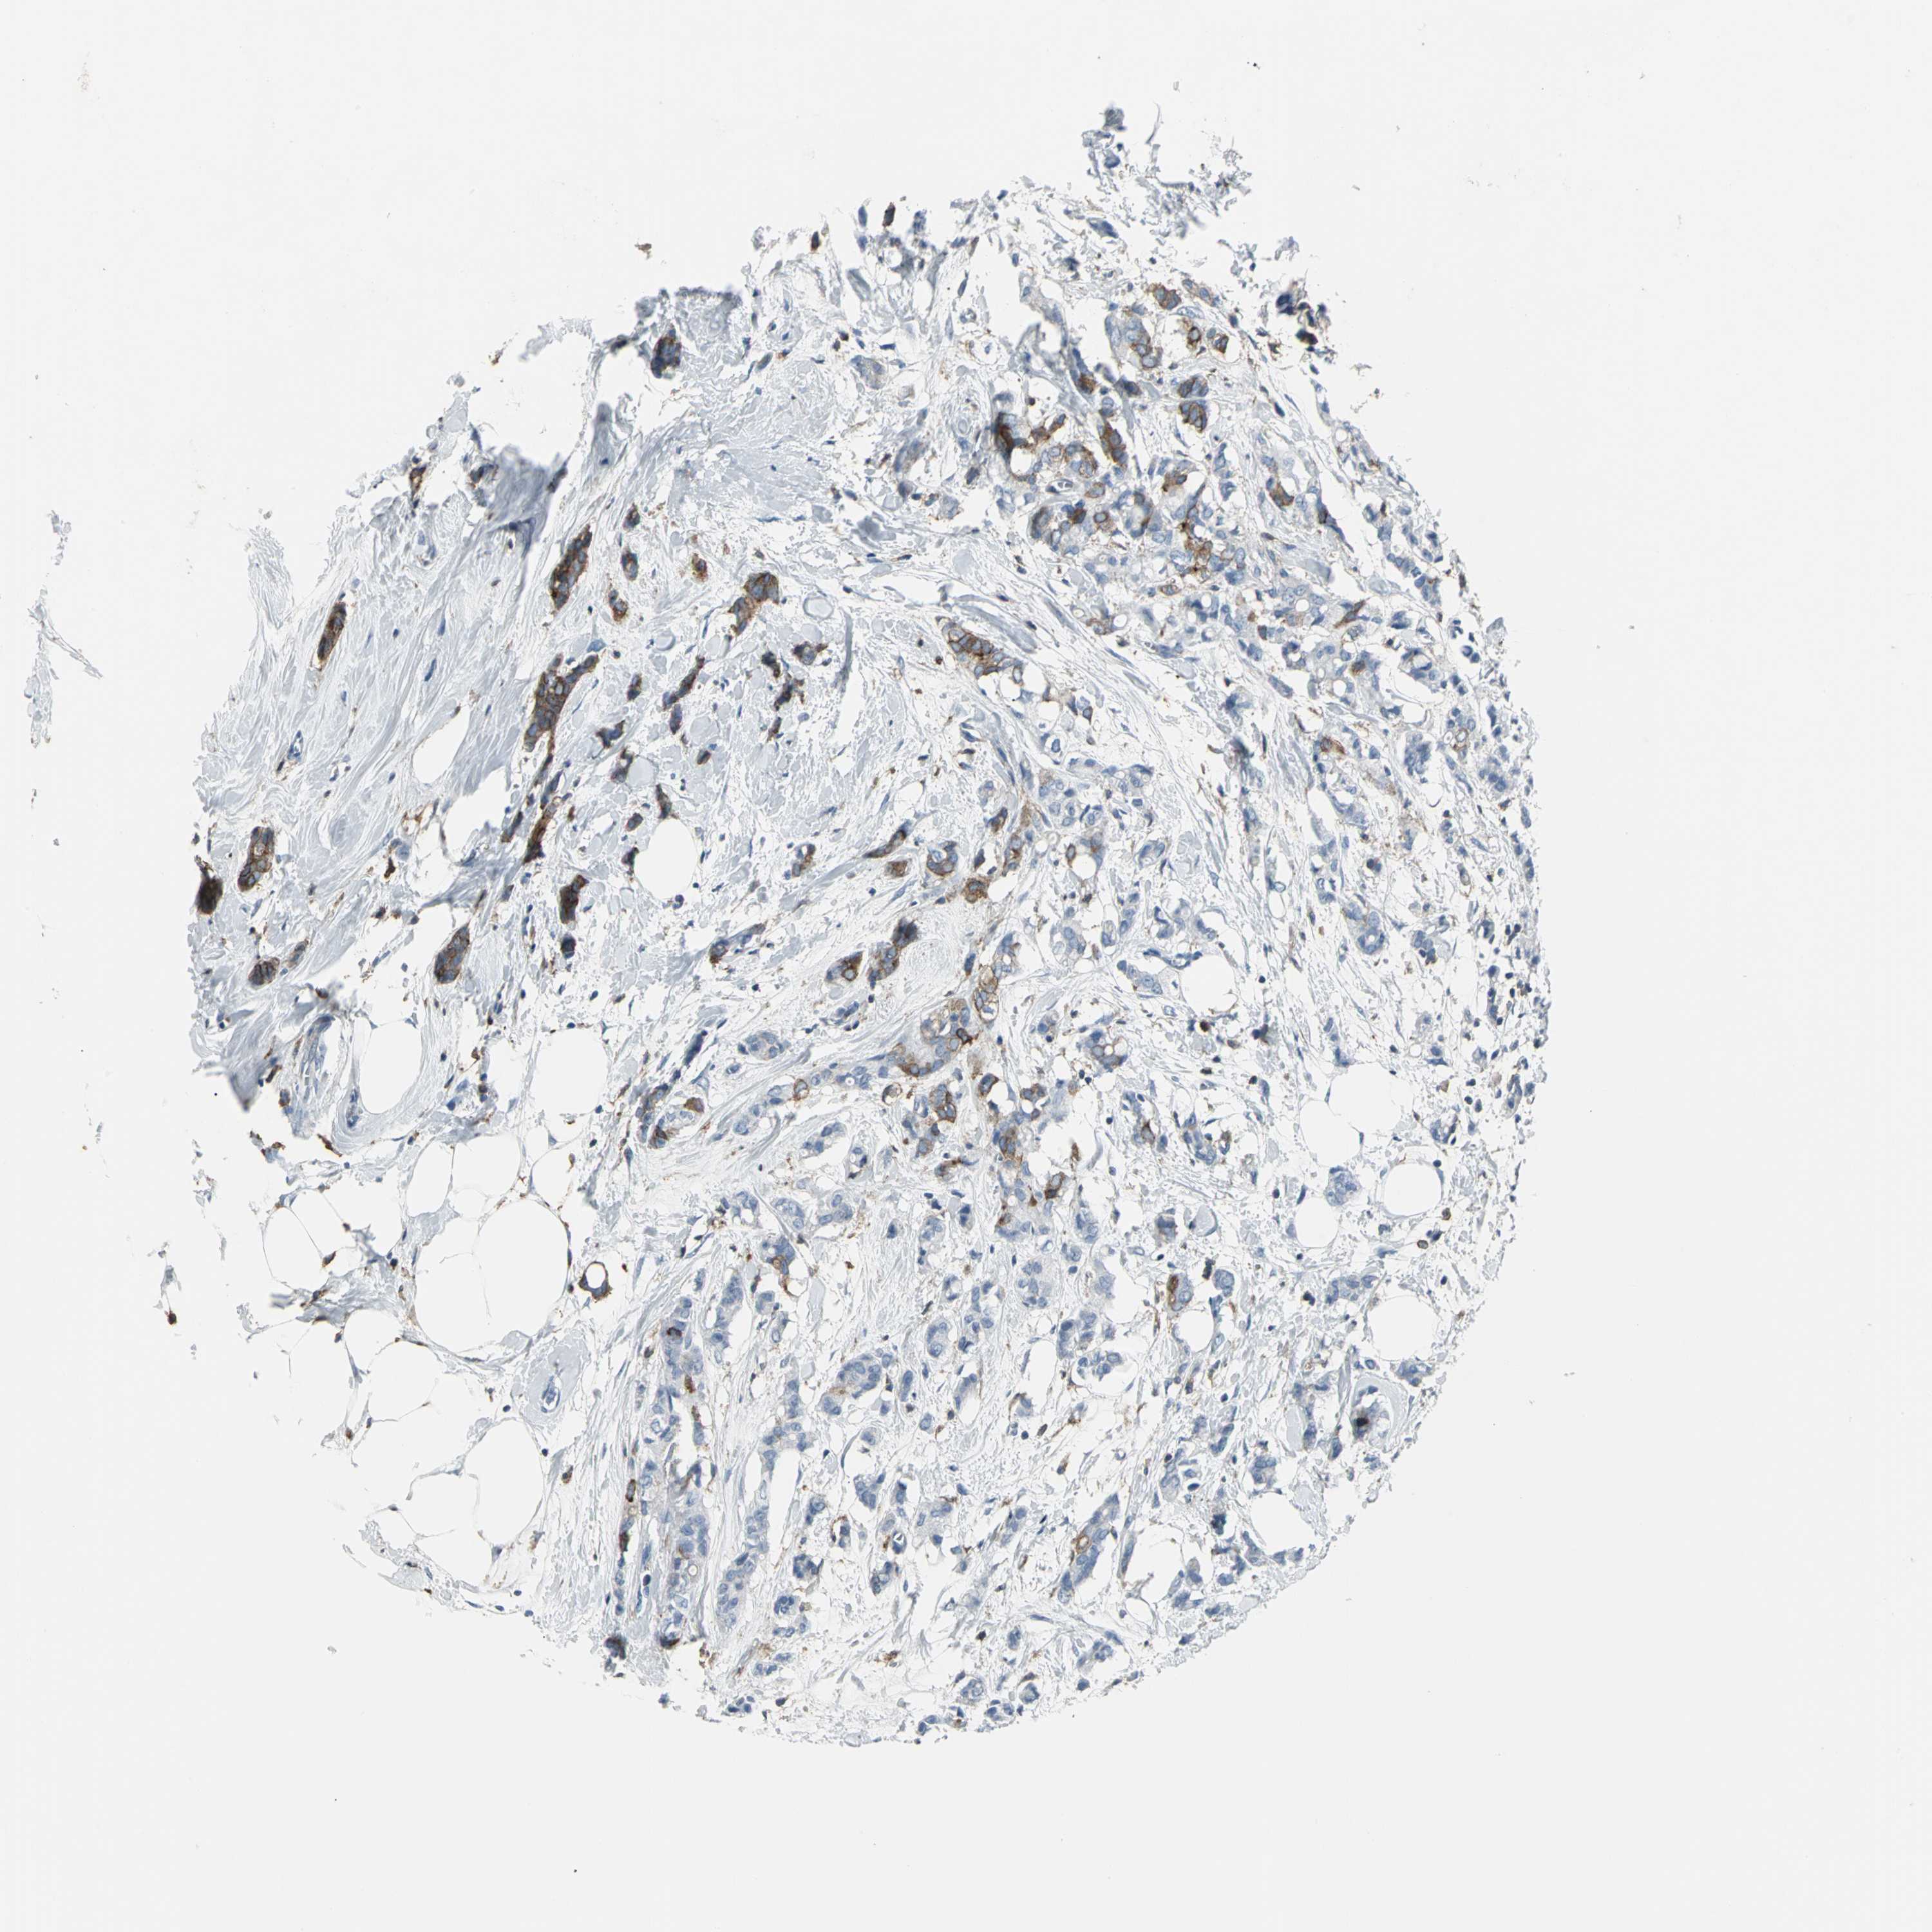

BRCA TCGA BRCA VALIDATION PROTEIN EXPRESSION